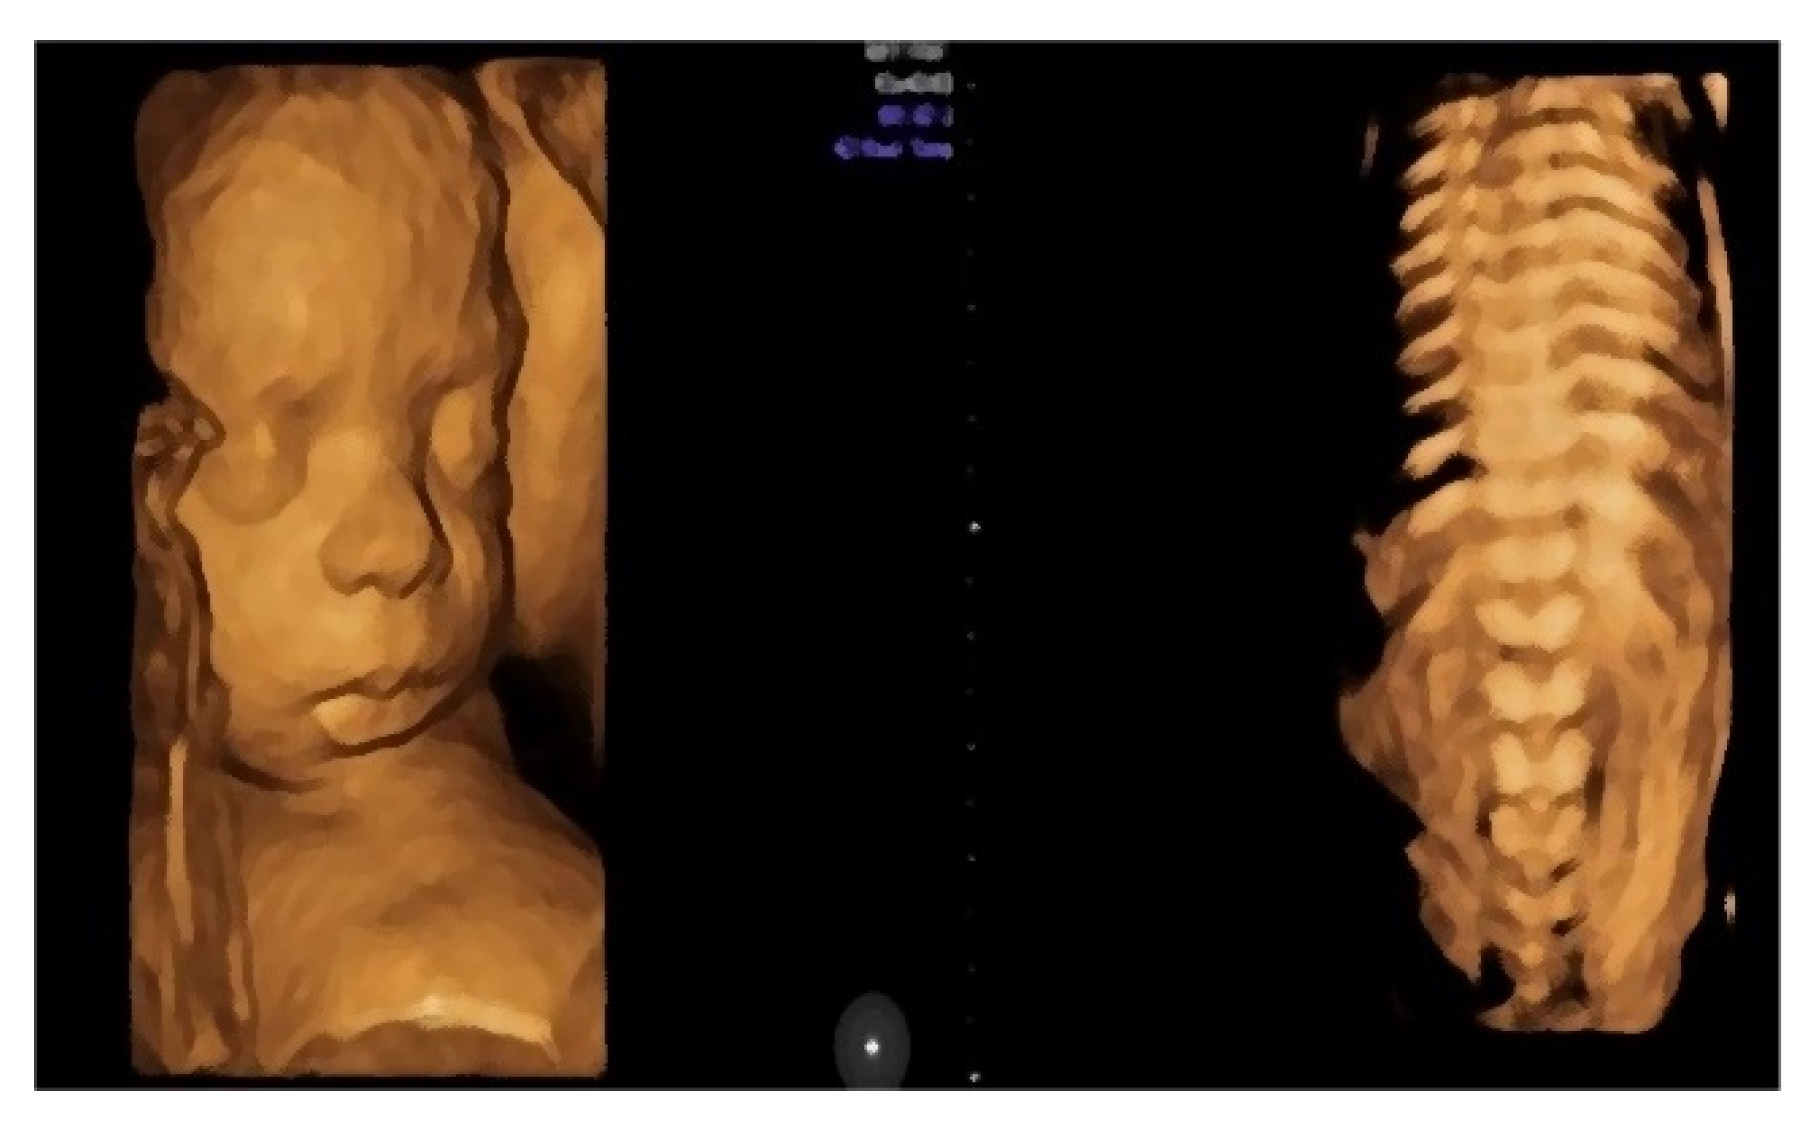

- Morphological examination during the 2nd trimester highlights the normal anatomy of the fetus (Figure 3).

- Muscular and skeletal diseases were excluded based on the presence of long bones with a normal shape and echogenicity without any visible asymmetry.

- A digestive system with a normal aspect: complete anterior abdominal wall, stomach in a left position under the diaphragm, normal fetal intestinal development with normal echogenicity.

- Central nervous system with no symmetric changes and a normal aspect. Complete fetal spine. No neural-tube defects were observed.